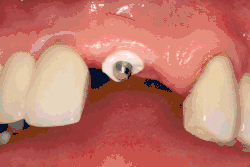

Bone loss (peri-implantitis) on implants over 7 years in a heavy smoker

Fixture show

Recession of the gingiva leads to exposure of the metal abutment under a dental crown.